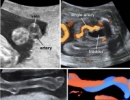

color doppler ultrasonography